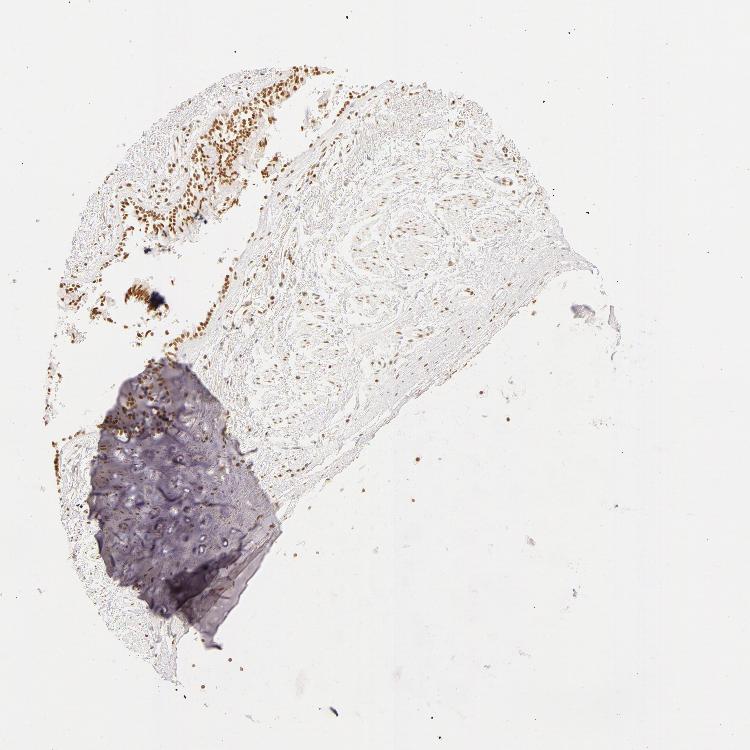

ADIPOSE TISSUE - Antibody stainingi

Antibody staining in the annotated cell types in the current human tissue is reported as not detected, low, medium, or high, based on conventional immunohistochemistry profiling in selected tissues. This score is based on the combination of the staining intensity and fraction of stained cells.

Each image is clickable and will lead to virtual microscopy that enables deeper exploration of all samples and also displays staining intensity scores, fraction scores and subcellular localization as well as patient and tissue information for each sample.

Antibody HPA001591

Adipocytes Medium